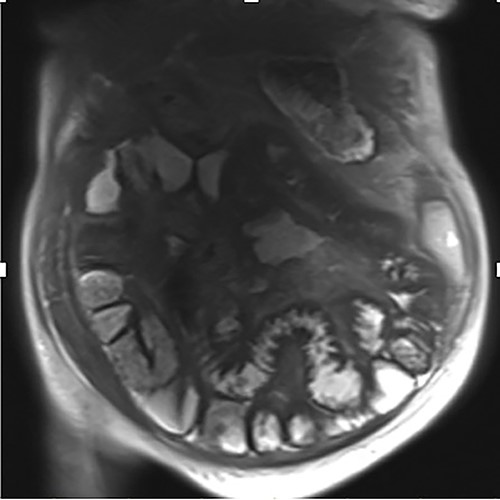

A 76-year-old lady presented to the outpatient clinic with a history of lower abdominal bloating and lethargy for 1 week. The patient denied abdominal pain, nausea, altered bowel habits or GI bleeding. Her past medical history included gastroesophageal reflux disease, ulcerative colitis and a previous hysterectomy. Physical examination exhibited pallor of the conjunctiva, distended abdomen with visible peristalsis on inspection but soft, non-tender on palpation and absence of ascites. Laboratory testing found normocytic normochromic anaemia, thrombocytosis and a positive myeloma screen with elevated kappa to lambda free light chain ratio despite normal renal and liver function. An ultrasound of the abdomen was unremarkable. Computed tomography (CT) with IV contrast of the abdomen revealed diffuse thickening of the small and large bowel with the small bowel dilated throughout. Magnetic resonance imaging of the small bowel showed multiple abnormally thickened loops of the jejunum and proximal ileum with a maximal wall thickness of 0.9 cm (Figs 1 and 2). Gastroscopy revealed severe distal oesophagitis, the stomach contained patchy telangiectasia and gastritis with sloughy mucosa at the incisura in addition to duodenitis with stricture at the second part of duodenum (D2) (Figs 3 and 4). Histopathology from the biopsies of the gastric incisura, D2 and the proximal jejunum displayed reactive changes with intramucosal haemorrhage and extensive deposition of pink amorphous, eosinophilic material on haematoxylin & eosin (H&E) stain. The deposits were predominantly seen in the proximal jejunum with a positive Congo red stain showing apple-green birefringence under polarized light (Figs 5 and 6). The patient was referred to Haematology, and a bone marrow aspirate and trephine biopsy revealed proliferation of 15% mature plasma cells consistent with the diagnosis of myeloma.

Endoscopic retroflexed view of the stomach showing gastritis, patchy telangiectasia and sloughy mucosa at the incisura.